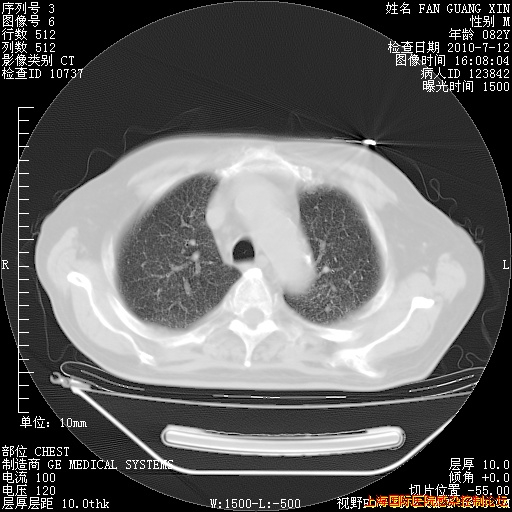

今天复查CT

今天CT

整整相隔30天的肺部CT好像有所好转啊。甲强龙减量第3天,需要观察体温。